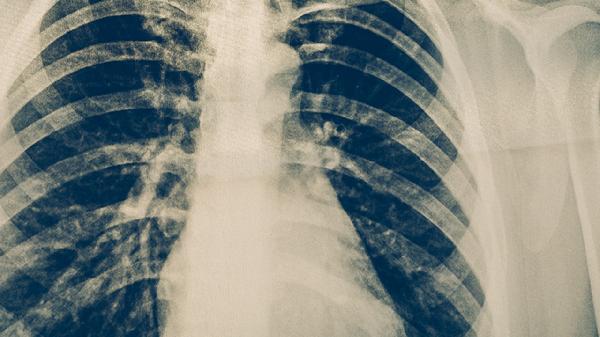

4。支气管扩张、肺脓疡、肺心病、肺结核患者出现咳嗽时应去医院就诊。